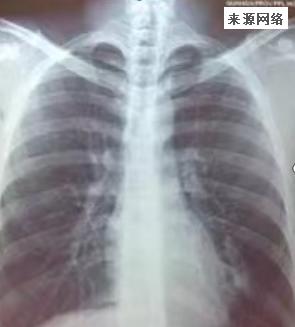

担心老人出现“大白肺”具体怎么观察

提前预警“白肺”有方法